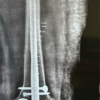

Figure 5: Railroad technique using prebent 2 low-profile 3.5 mm titanium locking plate fixation of transverse fracture of sternum.

The reduction was stabilized with K-wires. We then decided to use two low-profile 3.5 mm titanium locking plates in a railroad technique, pre-bending them to match the contour of the sternum (Fig. 5).